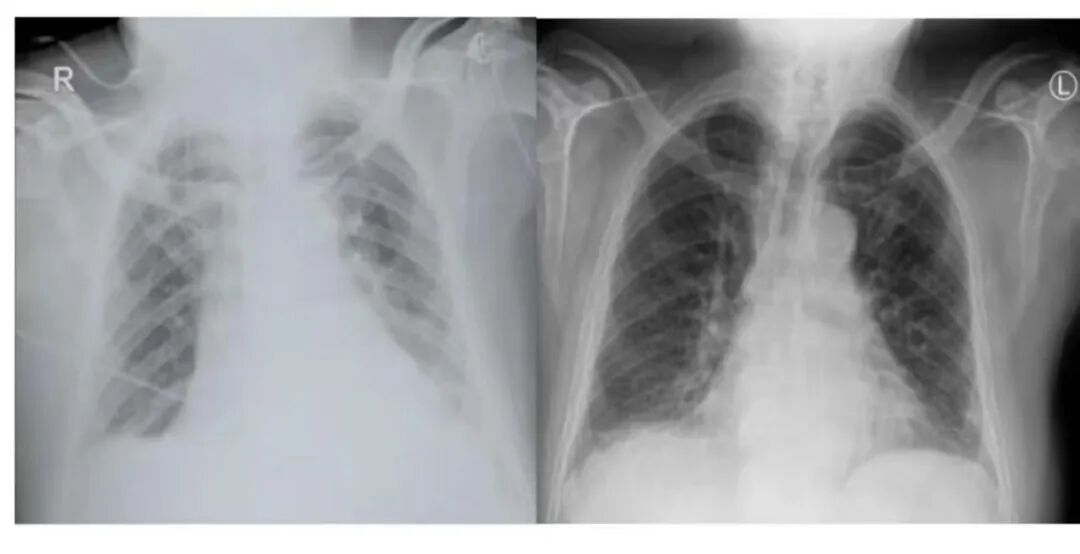

(图左)为床边拍摄胸片,清晰度及对病变的观察明显远不如放射科机房拍摄(图右)

总而言之,床边摄片只是不得已而为之,是机房摄片的补充,并不能完全替代机房摄片。

由于床旁摄片使用的是移动式X射线设备,技术参数比固定式设备的要求低,加上长期的移动和颠簸,其摄影质量会相对较差,图像质量可能不如传统X射线室的设备高,可能导致影像细节不够清晰,限制了医生对病情的准确判断;同时危重患者的各种监护设备,加之体位不正等因素也会影响图像质量。